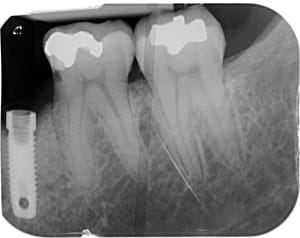

558904719_10163144646272247_6774572045327740986_n.jpg